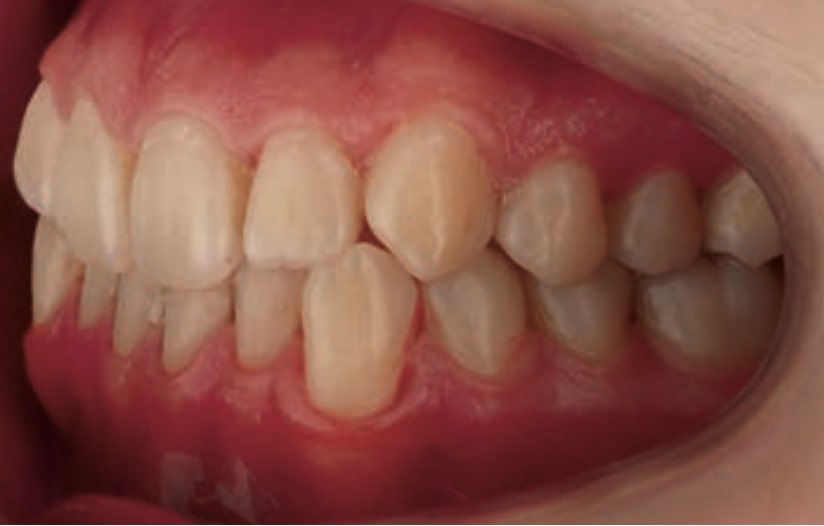

Chief complaint: The patient, a 19-year-old woman, was evaluated to undergo orthodontic treatment using the Angel Aligner Pro system. She presents with a skeletal Class III, mesofacial, with a dental Class III malocclusion and a 2 mm deviation of the lower midline to the left. Teeth 33 and 43 are out of the arch and cortical bone, with a crossbite issue on tooth 33. Fortunately, no functional issues affecting swallowing or breathing have been detected. The patient’s motivation for starting treatment was a general review of her dental and aesthetic health. The soft tissue analysis reveals mandibular protrusion that influences her facial profile. This diagnosis highlights the need for a comprehensive approach to address dental and skeletal misalignments, improving both the patient’s functionality and facial aesthetics.

• Dental Class III, 2 mm deviation of the lower midline to the left. 33 and 43 out of the arch and the cortical bone.

• Crossbite of 33.